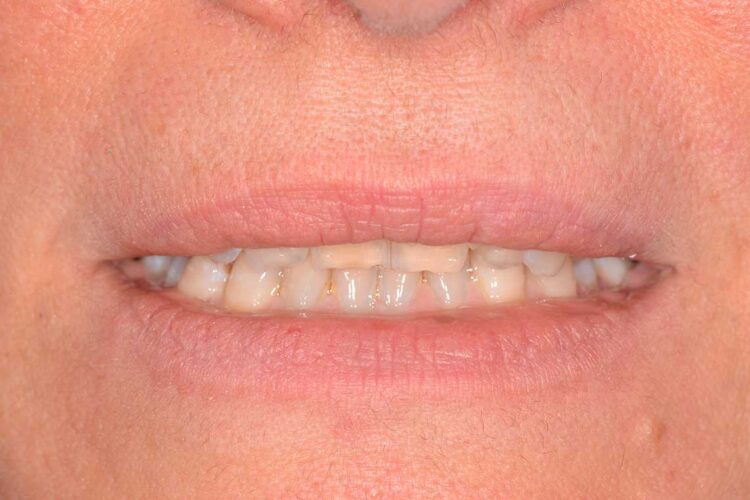

Ortodonzia allineatori – caso clinico 2